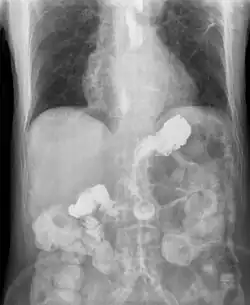

Mezi základní vyšetřovací metody patří 24h pH-metrie a terapeutický test s inhibitory protonové pumpy. Při pátrání po refluxní ezofagitidě či dalších komplikacích je nutné endoskopické (gastroskopie) vyšetření.